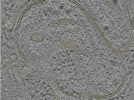

Photo Caption: Central slab from a representative tomogram of a Homo sapiens sample with selected set of annotations.

Cryo-electron tomography of FIB-milled HeLa PINK1-GFP cells treated with 10 uM Gamitrinib-triphenylphosphonium (G-TPP) for 4 hours to induce mitochondrial proteostatic stress. Data includes raw tilt series movie frames, assembled tilt series, tomographic reconstructions (WBP with and without CTF deconvolution), and automated segmentations of membranes. Acquired on a Titan Krios G4 with Falcon 4i detector and Selectris energy filter at 300 kV using dose-symmetric tilting with 3 degree increments. Cryo-FIB milling was performed on an Aquilos 2 cryo-FIB/SEM to produce lamellae of less than 250 nm thickness.